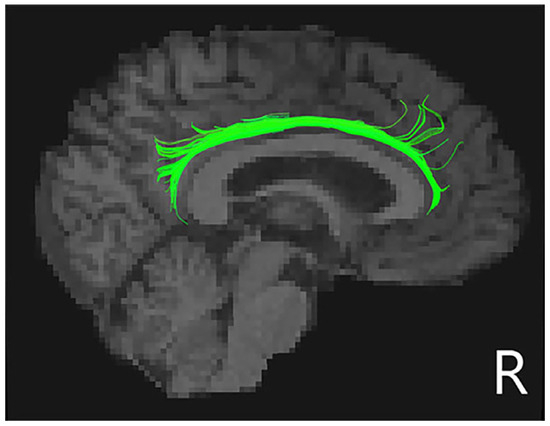

3.3. White Matter Tracts

| Tract | PD-No-Punding (n = 19) | PD-Punding (n = 19) | p-Value | |

|---|---|---|---|---|

| FA | R_CCing | 0.500 ± 0.027 | 0.470 ± 0.026 | 0.006 * |

| L_IFOF | 0.458 ± 0.018 | 0.446 ± 0.018 | 0.039 a | |

| R_SLF | 0.534 ± 0.041 | 0.507 ± 0.046 | 0.023 a | |

| MD (×10−3 mm2 s−1) | R_CCing | 0.692 ± 0.032 | 0.720 ± 0.041 | 0.038 a |

| R_UF | 0.793 ± 0.044 | 0.825 ± 0.044 | 0.010 a |